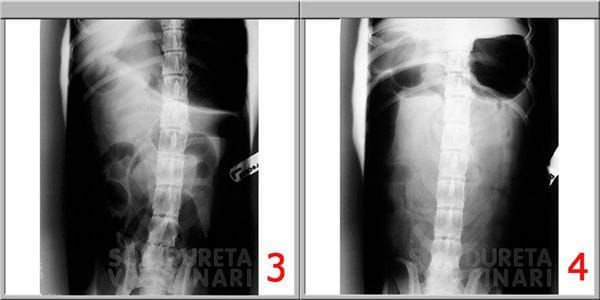

Pancho requería una actuación veterinaria intensiva y urgente, inmediatamente se administraron fluidos por vía intravenosa y una transfusión de plasma, con el objetivo de corregir su deshidratación, coagulación y restaurar su volumen de líquido circulante. Le aplicamos calor para recuperar su temperatura corporal y toda la medicación de apoyo necesaria para ayudar a su estómago e intestinos a recuperarse (protectores gástricos, antibióticos, analgésicos, protectores hepáticos y vitaminas).

Tras cinco días de hospitalización en cuidados intensivos pudimos darle el alta hospitalaria y seguir en hogar con la medicación. Pancho se ha recuperado bien, ya vuelve a estar alegre, con ganas de pasear, y por supuesto de comer.